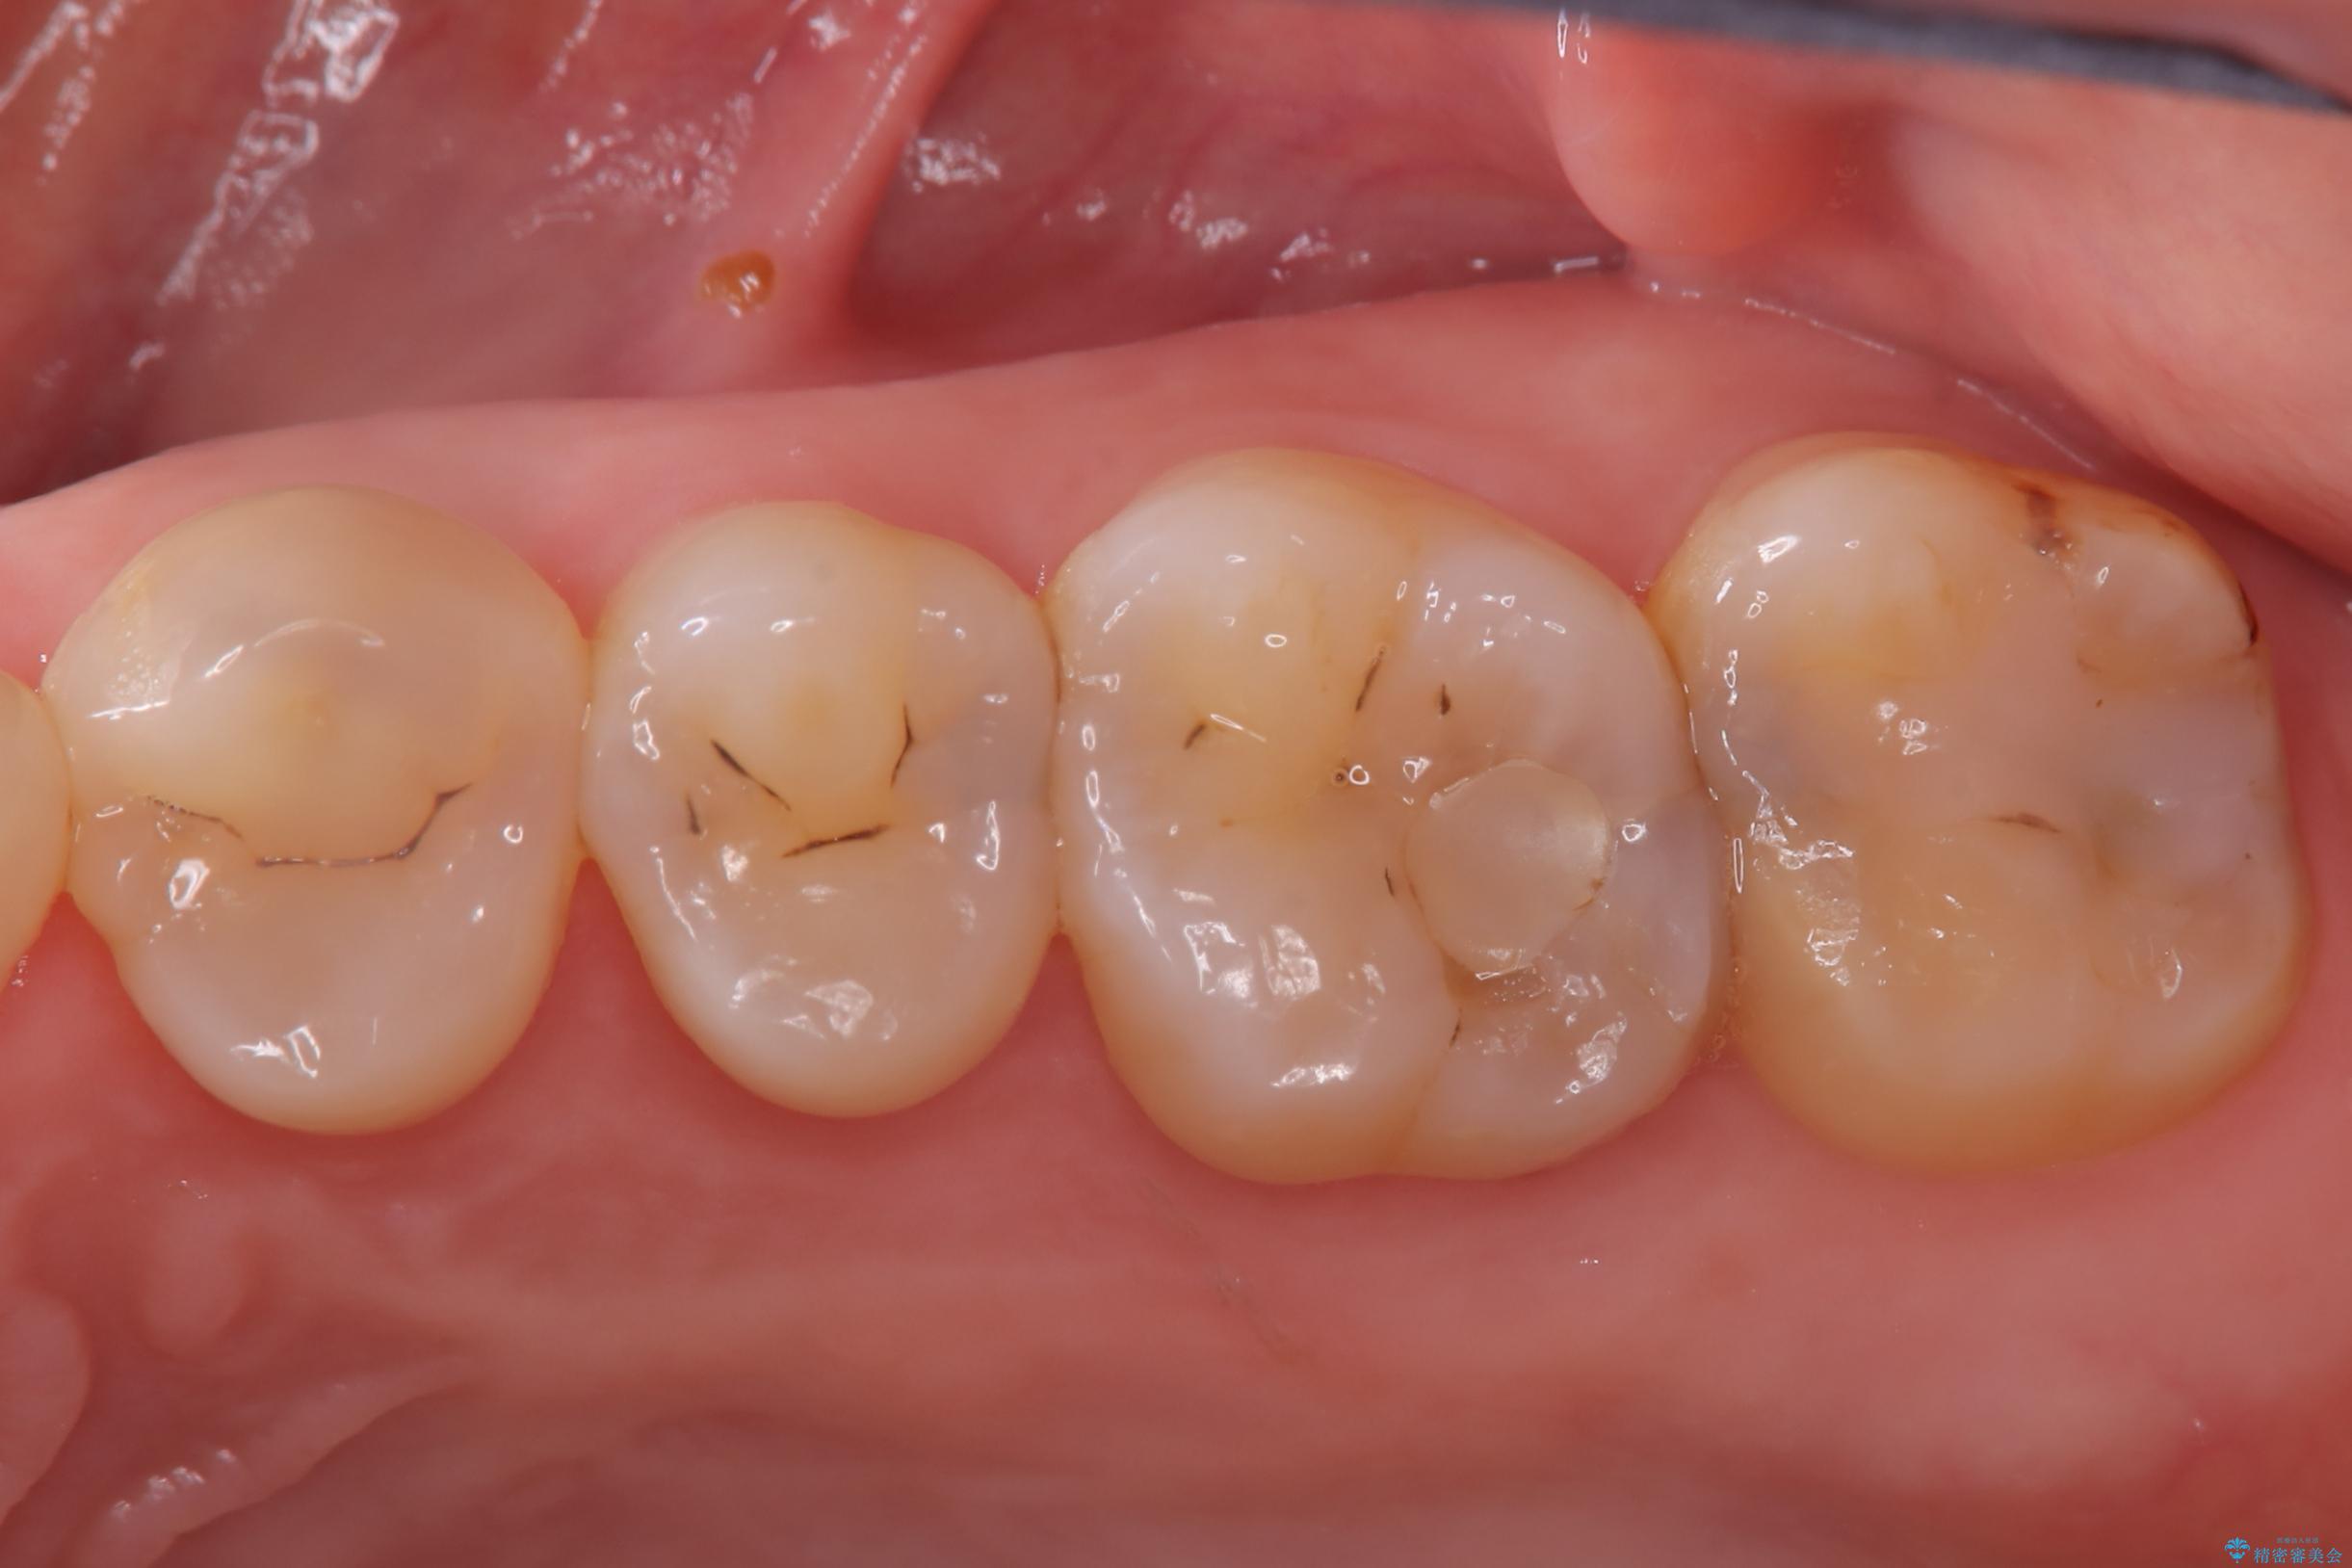

2回で完了した奥歯のセラミック修復

- 奥歯の虫歯治療を主訴にご来院されました。患者様から「できるだけ通院回数を少なく、早く治療を終わらせたい」というご要望があったため、短期間での完了を目指し、セラミックインレー(詰め物)とセラミッククラウン(被せ物)を併用する治療計画を立案しました。治療は精密機器を活用し、2回の来院で最終的なセラミック修復物を装着することを目指します。

今回の治療では、虫歯の大きさや深さに応じて、異なるセラミック修復法を適用しました。

比較的軽度な虫歯には、セラミックインレー(詰め物)で対応し、健全な歯質を最大限に残しました。

進行した虫歯や歯の強度が低下している歯には、セラミッククラウン(被せ物)を選択し、歯全体を保護することで破折を防ぎました。

短期間での治療を可能にしつつ、天然歯と見分けがつかない審美性と、長期的に安定する機能性を兼ね備えたセラミック修復を実現しました。